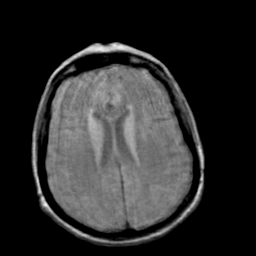

Creutzfeld-Jakob disease: proton density-weighted MR -- Slice #15

[Home][Help][Clinical] Slice 15